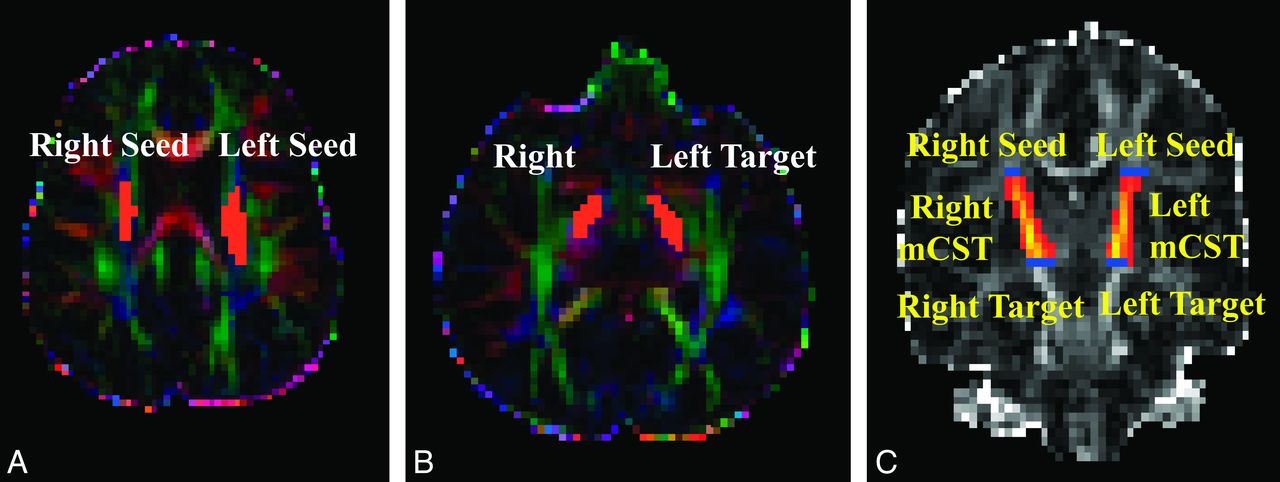

At each voxel, the Bayesian Estimation of Diffusion Parameters Obtained by using Sampling Techniques (BEDPOSTX) function in FSL was used to build up the distributions on diffusion parameters on the basis of the Markov Chain Monte Carlo sampling.11 The outputs of the BEDPOSTX were used to compute the PDT by using Probtrackx12 in FSL. The seed and target masks used in the PDT for genu of the CC were created on sagittal sections as illustrated in Fig 1. The 2 masks for the left or right mCST were created on axial sections placed between 1 section below the body of the corpus callosum and the entry of the posterior limb of the internal capsule to the cerebral peduncle (Fig 2). All masks were delineated by 1 operator (W.Y.) and confirmed by 3 pediatric radiologists (R.C.M., J.S.S., and B.V.J.) and 2 pediatric neurosurgeons (F.T.M., D.D.L.).

DTI maps demonstrating seed and target masks and resultant probabilistic fiber tracking of the left and right midsegments of the cortical spinal tracts in representative participants. A–C, Hydrocephalus. A and B, Color-coded FA maps. C, FA map. The masks shown in orange on the axial DTI maps can be seen as short blue lines on coronal FA map.

The connectivity index maps (Figs 1 and 2) are the connectivity distribution maps with the value at each voxel being the sum of the sample streamlines passing through the voxel. In the present study, we defined a seed mask and a target mask for each subject on the basis of anatomic landmarks, to restrict the tractography in all the tracts examined to yield the specific tracts of interest. The connectivity measure is a quantification of the strength, or probability, of the connectivity for all those connections initiated from the seed voxels and reaching the target masks. Similar approaches based on PDT have been adopted by other studies to investigate the pathologic progression in amyotrophic lateral sclerosis,14 to contrast the organization of prefrontal projection pathways in humans and macaque monkeys.20

In the present study, the histogram based on the aggregated normalized CI measures showed that children with hydrocephalus had a lower percentage of voxels with higher connectivity and a higher percentage of voxels with low connectivity in all 3 tracts examined. The comparison of the within-tract summary connectivity measure between the 2 groups showed a consistent significant decrease in normalized CI values in children with hydrocephalus. As expected, examination of the connectivity index maps (Figs 1 and 2 as examples) showed that the voxels with high connectivity were located in the central portion of the tracts, while the voxels at the peripheral areas of a tract tended to have lower connectivity. We examined the summary connectivity measure (normalized CI) not only at the median but also at the lower and upper quartile values. The fact that the group contrast was significant at all 3 quartile levels indicates that this summary connectivity index, normalized CI, is sensitive to the pathology resulting from hydrocephalus throughout different portions of WM tracts in children with hydrocephalus.